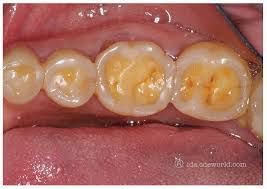

Dental erosion, also known as tooth erosion, is the chemical loss of mineralized tooth substance caused by exposure to acids not derived from oral bacteria. 1. Erosive demineralization is a chemical process characterized by acid dissolution of dental hard tissue, and its etiology is multifactorial.